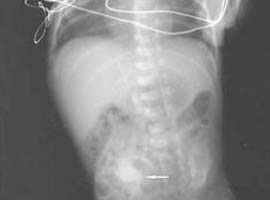

Viyana havaalanında uyuşturucu kaçakçılığı zanlısı bir Kosta Ricalının, midesinde 143 paket kokainle yakalandığı bildirildi.

Avusturya polisi, Kosta Ricalı zanlının midesinde yaklaşık 1 kilogram ağırlığındaki 143 paket kokainin X-ray cihazında tespit edildiğini kaydetti. Kosta Rica’nın başkenti San Jose’den Fransa’nın başkenti Paris’e, oradan da Viyana’ya uçan uyuşturucu kaçakçısı zanlının, yetkililere, uyuşturucu için kendisine ödenecek miktarın 2 bin dolar olduğunu söylediği belirtildi.